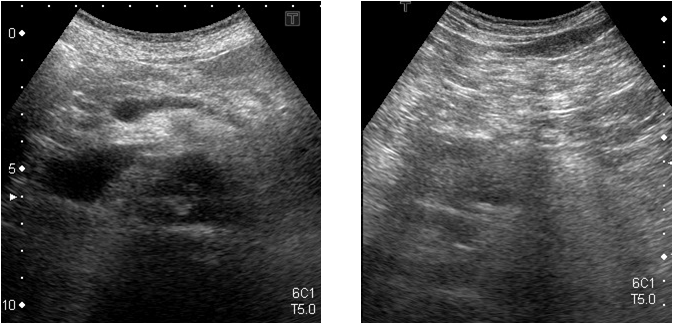

HOT ! 消化器超音波診断 : over lay方式 : 腹部エコーの描出手技と読影 Dr.小川の腹部エコーのWaza-ari!!<消化管編> | GE HealthCare (Japan)

消化器超音波診断 : over lay方式 : 腹部エコーの描出手技と読影 Dr.小川の腹部エコーのWaza-ari!!<消化管編> | GE HealthCare (Japan)の詳細情報

Dr.小川の腹部エコーのWaza-ari!!<消化管編> | GE HealthCare (Japan)。超音波でみる病気の腸(小腸・大腸)」腹部超音波検査Vol.9-2 | みどり。超音波でみる病気の腸(小腸・大腸)」腹部超音波検査Vol.9-2 | みどり。オーバーレイ方式 消化器超音波診断 OVER LAY方式 腹部エコーの描出手技と読影新日本法規 1988年初版約 32.2 x 23.4 x 7 cm約 2.3kg監修 中澤三郎 名古屋大学医学部 第二内科助教授著者 木本英三/内藤靖夫 名古屋大学医学部 第二内科函入 上製本定価 38,000円箱に傷や汚れがあります。#腹部エコー#超音波#超音波診断#オーバーレイ。腹部エコー検査方法 「腹部超音波検査のやり方」